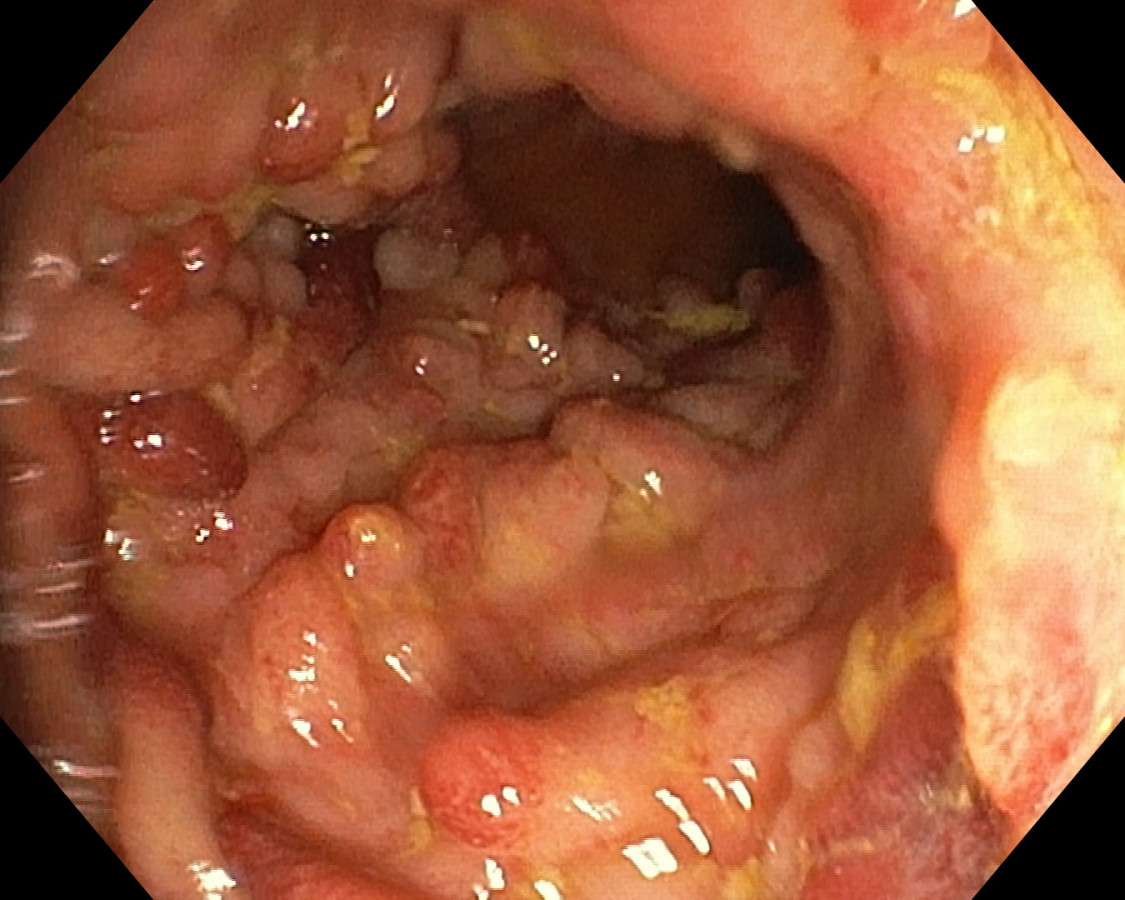

Polypóza u pacienta s ulceróznou kolitídou

Pacient s UC - dg. od r. 2009 ako pankolitída, od 4/2010 pri imunosupres. th. kompletná remisia ochorenia, už vtedy pseudopolypózne štádium, noncompliance, kontrola až pri relapse v r. 2017. Odvtedy +/- chodí na kontroly. 07/2023 relaps, systémové kortikosteroidy, ATB, s efektom - 9/2023 pankolonoskopia - pravostranne nález dobrý, ľavá strana síce bez aktivity ochorenia, aj histolog. remisia, ale polypózne št. hlavne v sigme - foto - dysplázia zachytená nebola. Bude ťažké odsledovať KRCA v tomto teréne. Dalo by sa uvažovať o chirurgickej liečbe ? Ďakujem.

U nemocných s UC je výskyt zánětlivé polypózy, kterou rozumíme přítomnost více než deseti zánětlivých polypů, relativně častý. Je odrazem těžce probíhající zánětu. Zánětlivé polypy nemají sami o sobě potenciál maligní degenerace a v tomto ohledu není potřeba je kontrolovat nebo odstraňovat. Mnohočetné zánětlivé polypy však znesnadňují průběh dispenzárních koloskopických prohlídek, protože významně omezují přehlednost po sliznici a detekci dysplastických změn. Druhý negativní dopad vícečetných zánětlivých polypů je u udržování aktivního zánětu a elevaci hodnot fekálního kalprotektinu. U nemocných s mnohočetnými zánětlivými polypy v rektu a rekto-sigmatu mohou být persistující tenesmy a intermitentní krvácení vyvolány právě jejich přítomností. V těchto případech je endoskopicky odstraňujeme.